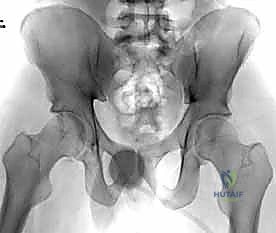

4. الرد المفتوح (Open Reduction)

بعد تنظيف المفصل من أي أنسجة متمزقة أو جلطات دموية، يتم استخدام ملاقط عظمية خاصة (Pelvic Reduction Forceps) لجذب عظام العانة المنفصلة وإعادتها إلى موضعها التشريحي الصحيح بدقة مليمترية.

5. التثبيت الداخلي (Internal Fixation)

بمجرد استعادة الوضع الصحيح للعظام، يقوم الدكتور هطيف بتثبيتها باستخدام صفيحة معدنية متخصصة (غالباً صفيحة إعادة بناء متعددة الثقوب مصنوعة من التيتانيوم أو الفولاذ المقاوم للصدأ الطبي). يتم تثبيت هذه الصفيحة عبر المفصل العاني باستخدام مسامير قشرية (Cortical Screws) تُغرس بعمق في عظام العانة الصلبة لضمان تثبيت قوي يتحمل ضغط الجسم.